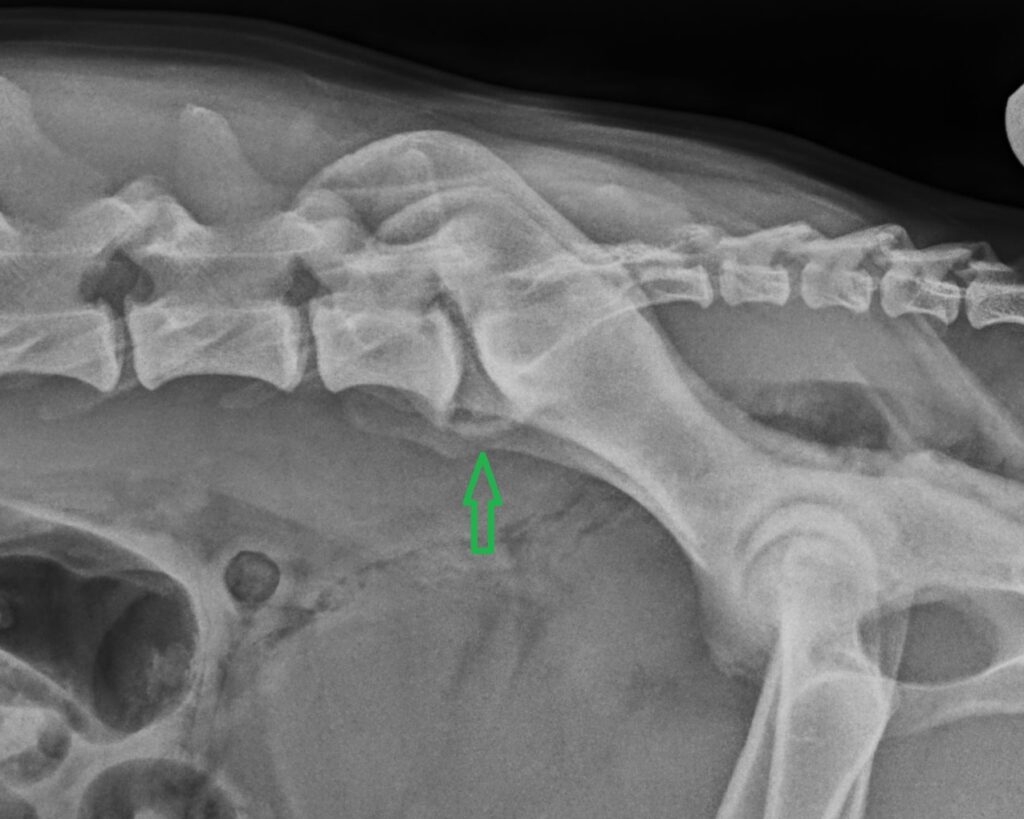

Lumbosacral Disease in Dogs

Lumbosacral Disease refers to a degenerative condition at the junction between the last lumbar vertebra (lower spine) and the sacrum (pelvis). In simple terms, it’s a problem that affects the nerves leaving the lower back, leading to pain, stiffness, and mobility issues.